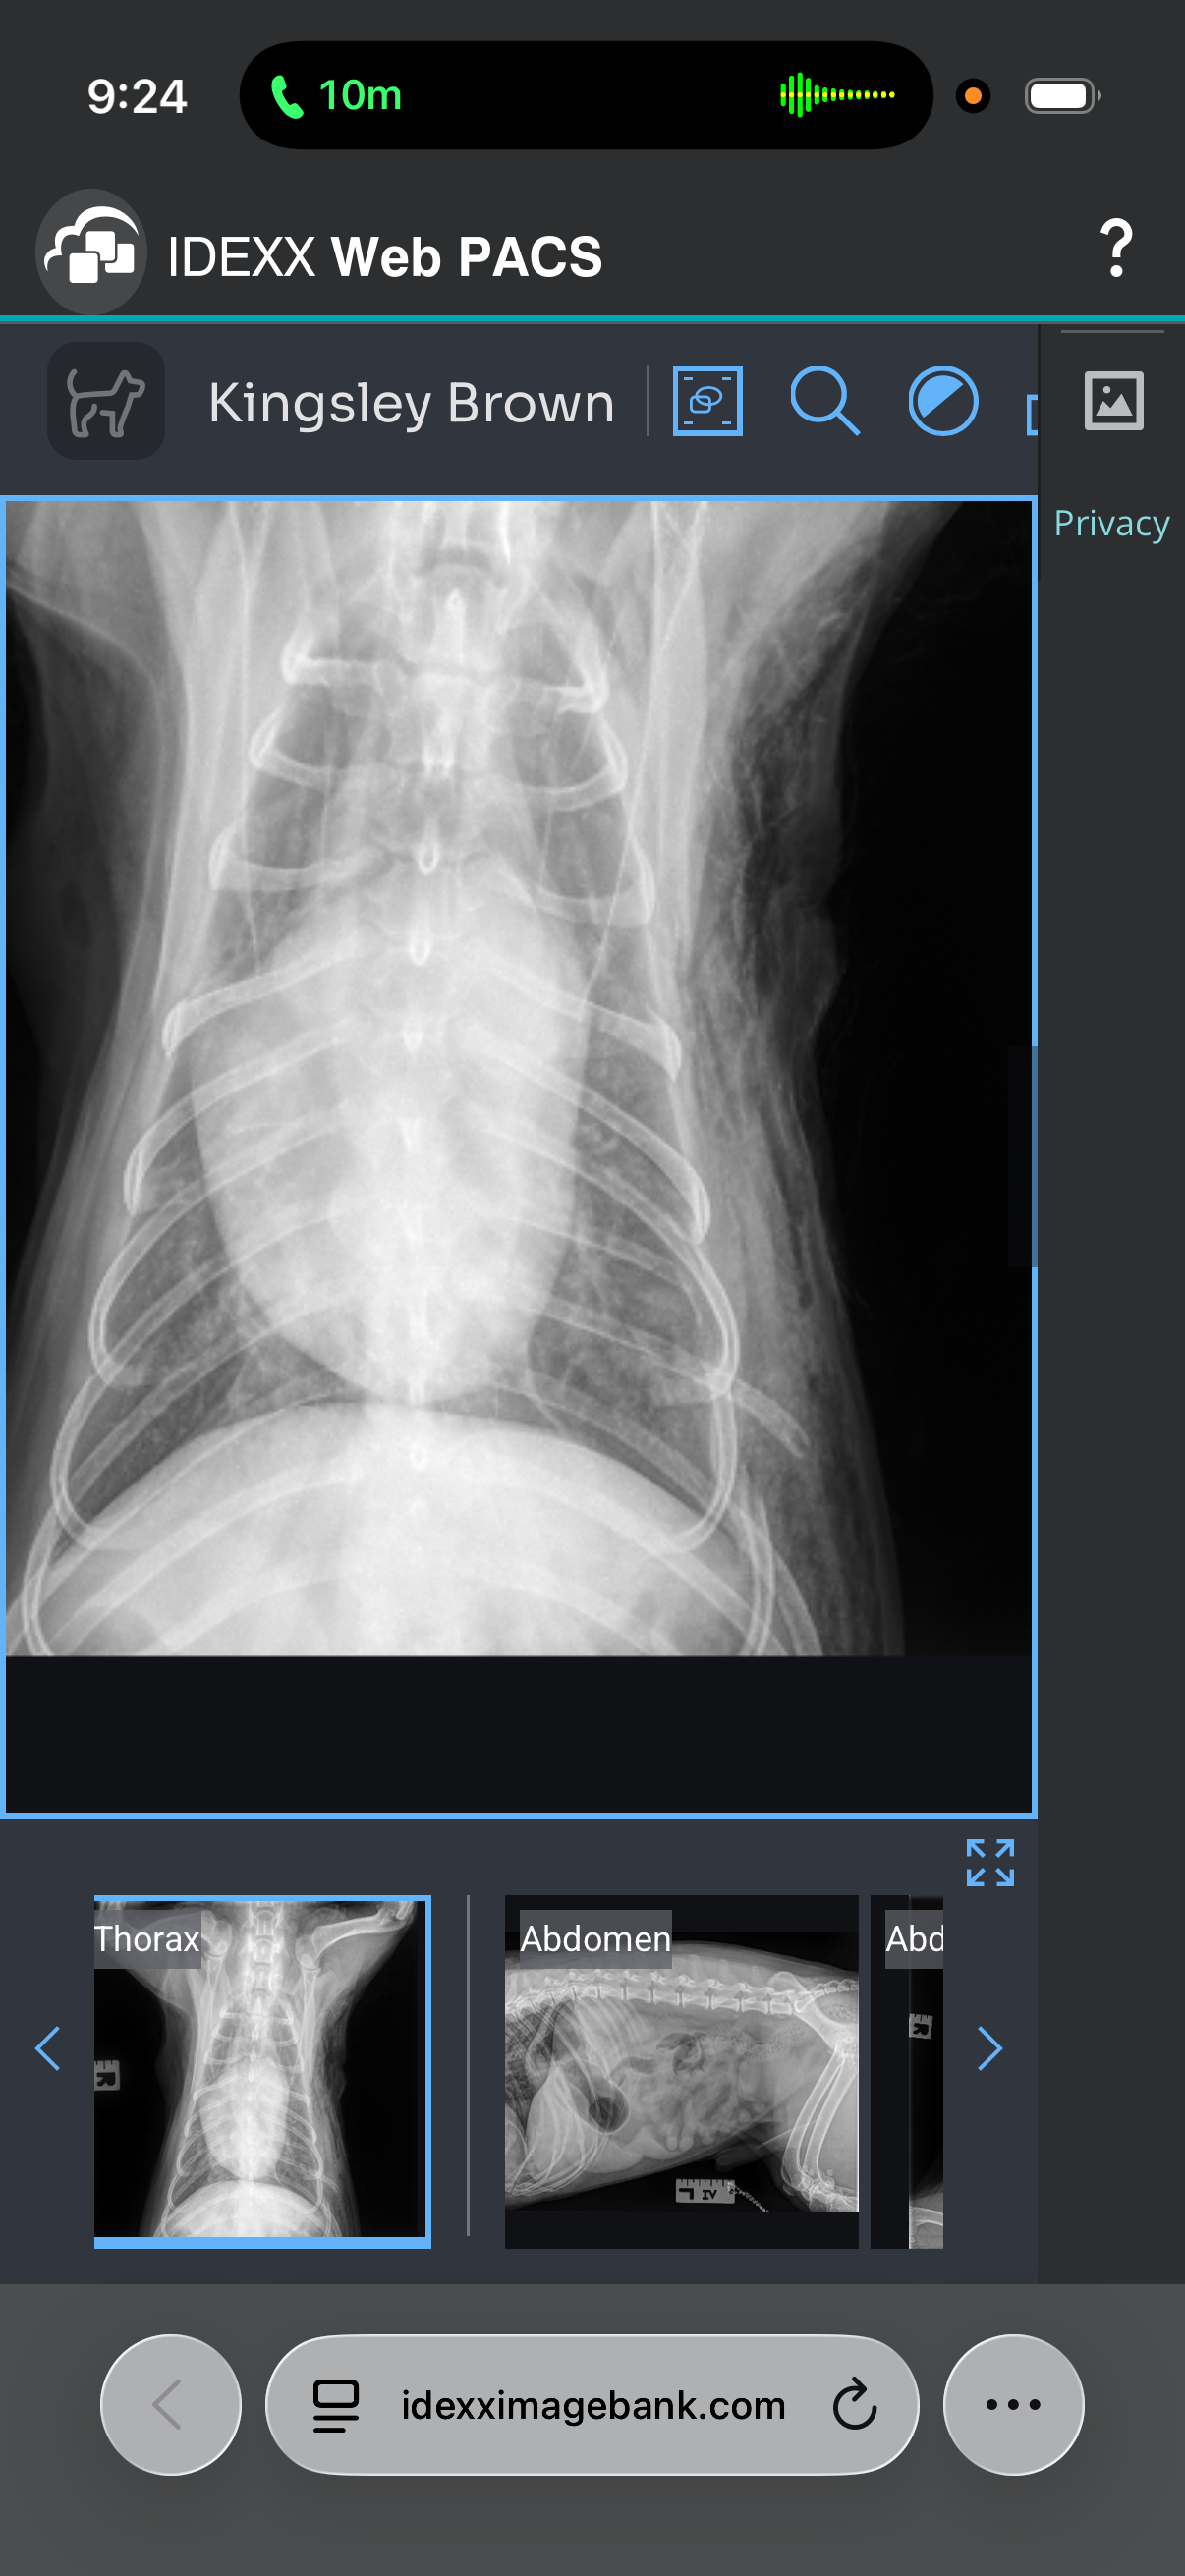

Hey everyone my friend Ashley Brown and her 5 year old son went through a tragic event on Christmas Day! They were walking there sweet dog Kingsley , when out of no where two pit bulls came up to them and attacked the dog . He has had surgeries to repair the the side of him and his neck they attacked . He has three broken ribs and draining tubes . He had a seizure today and back to the hospital . She is a single Mom and has spent all of her money to save her dogs life . If anyone can help donate towards medical bills and food for them that would be awesome! Thanks so much for considering to help this sweet family !